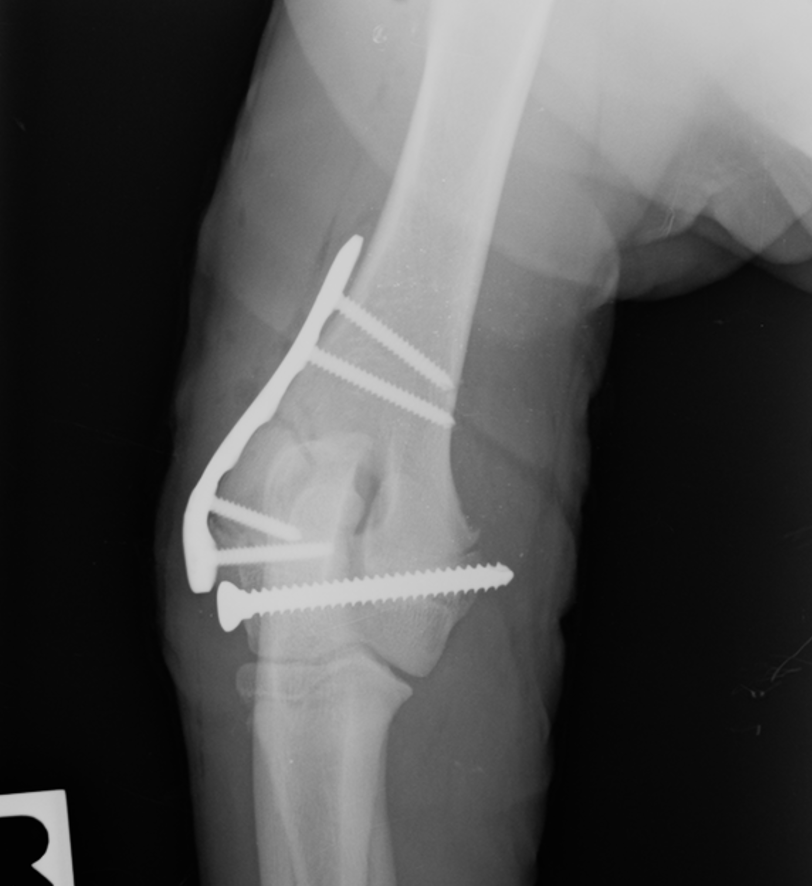

Cranial Closing Wedge Osteotomy (CCWO) is the universal surgery to manage canine cranial cruciate ligament disease. Suitable for dogs large and small, young and old it offers flexibility beyond any other tibial osteotomy technique.

In the morning session we cover the key objectives before practicing the technique on saw bone and then in the wet lab for a hands-on practical. Learn patient assessment, pre-operative planning, implant selection, instrumentation, postoperative care, and complication handling. Gain hands-on experience through dry and wet lab sessions for confident surgical execution.

• To understand the biomechanics of the cruciate ligament deficient stifle and cranial closing wedge osteotomy